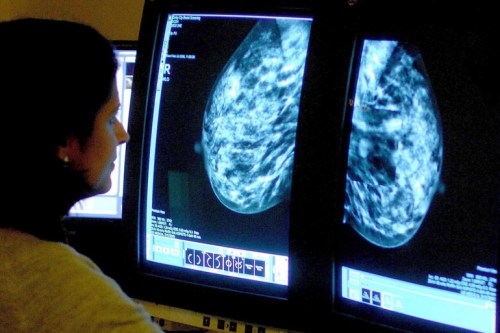

The American Cancer Society’s new breast cancer screening guidelines recommend that women start screening later and get fewer mammograms, but the change is unlikely to affect insurance coverage anytime soon.

The updated guidelines, which were published in the Journal of the American Medical Association this week, recommend that women who are at average risk for breast cancer start annual mammograms at age 45 and continue until age 54, then reduce screening frequency to once every two years. They should continue on that schedule as long as their life expectancy is at least 10 years. The ACS also no longer recommends that women receive manual clinical breast exams.

The previous guidelines, which had been in place since 2003, recommended annual mammograms and clinical breast exams starting at age 40 for women who were at average risk.